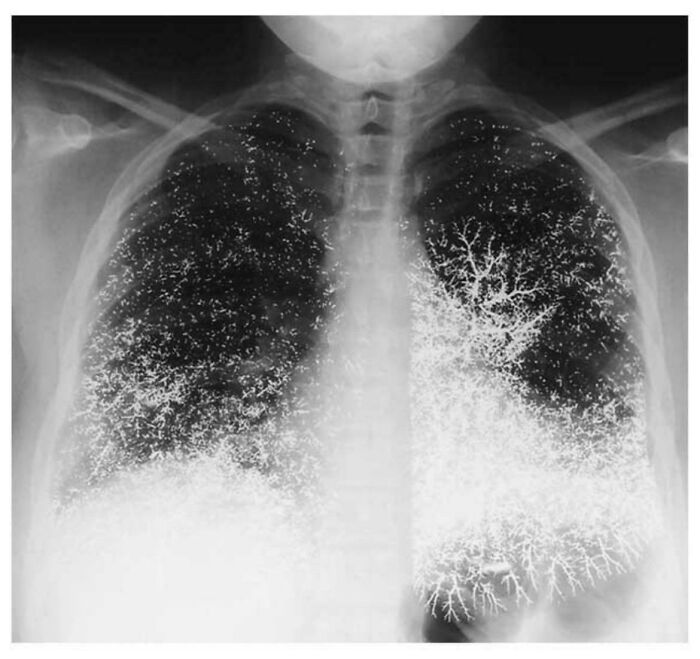

Chest X-Ray Of 21 Yr Old Dental Assistant After Attempting To Take Their Own Life By Intravenously Injecting Elemental Mercury